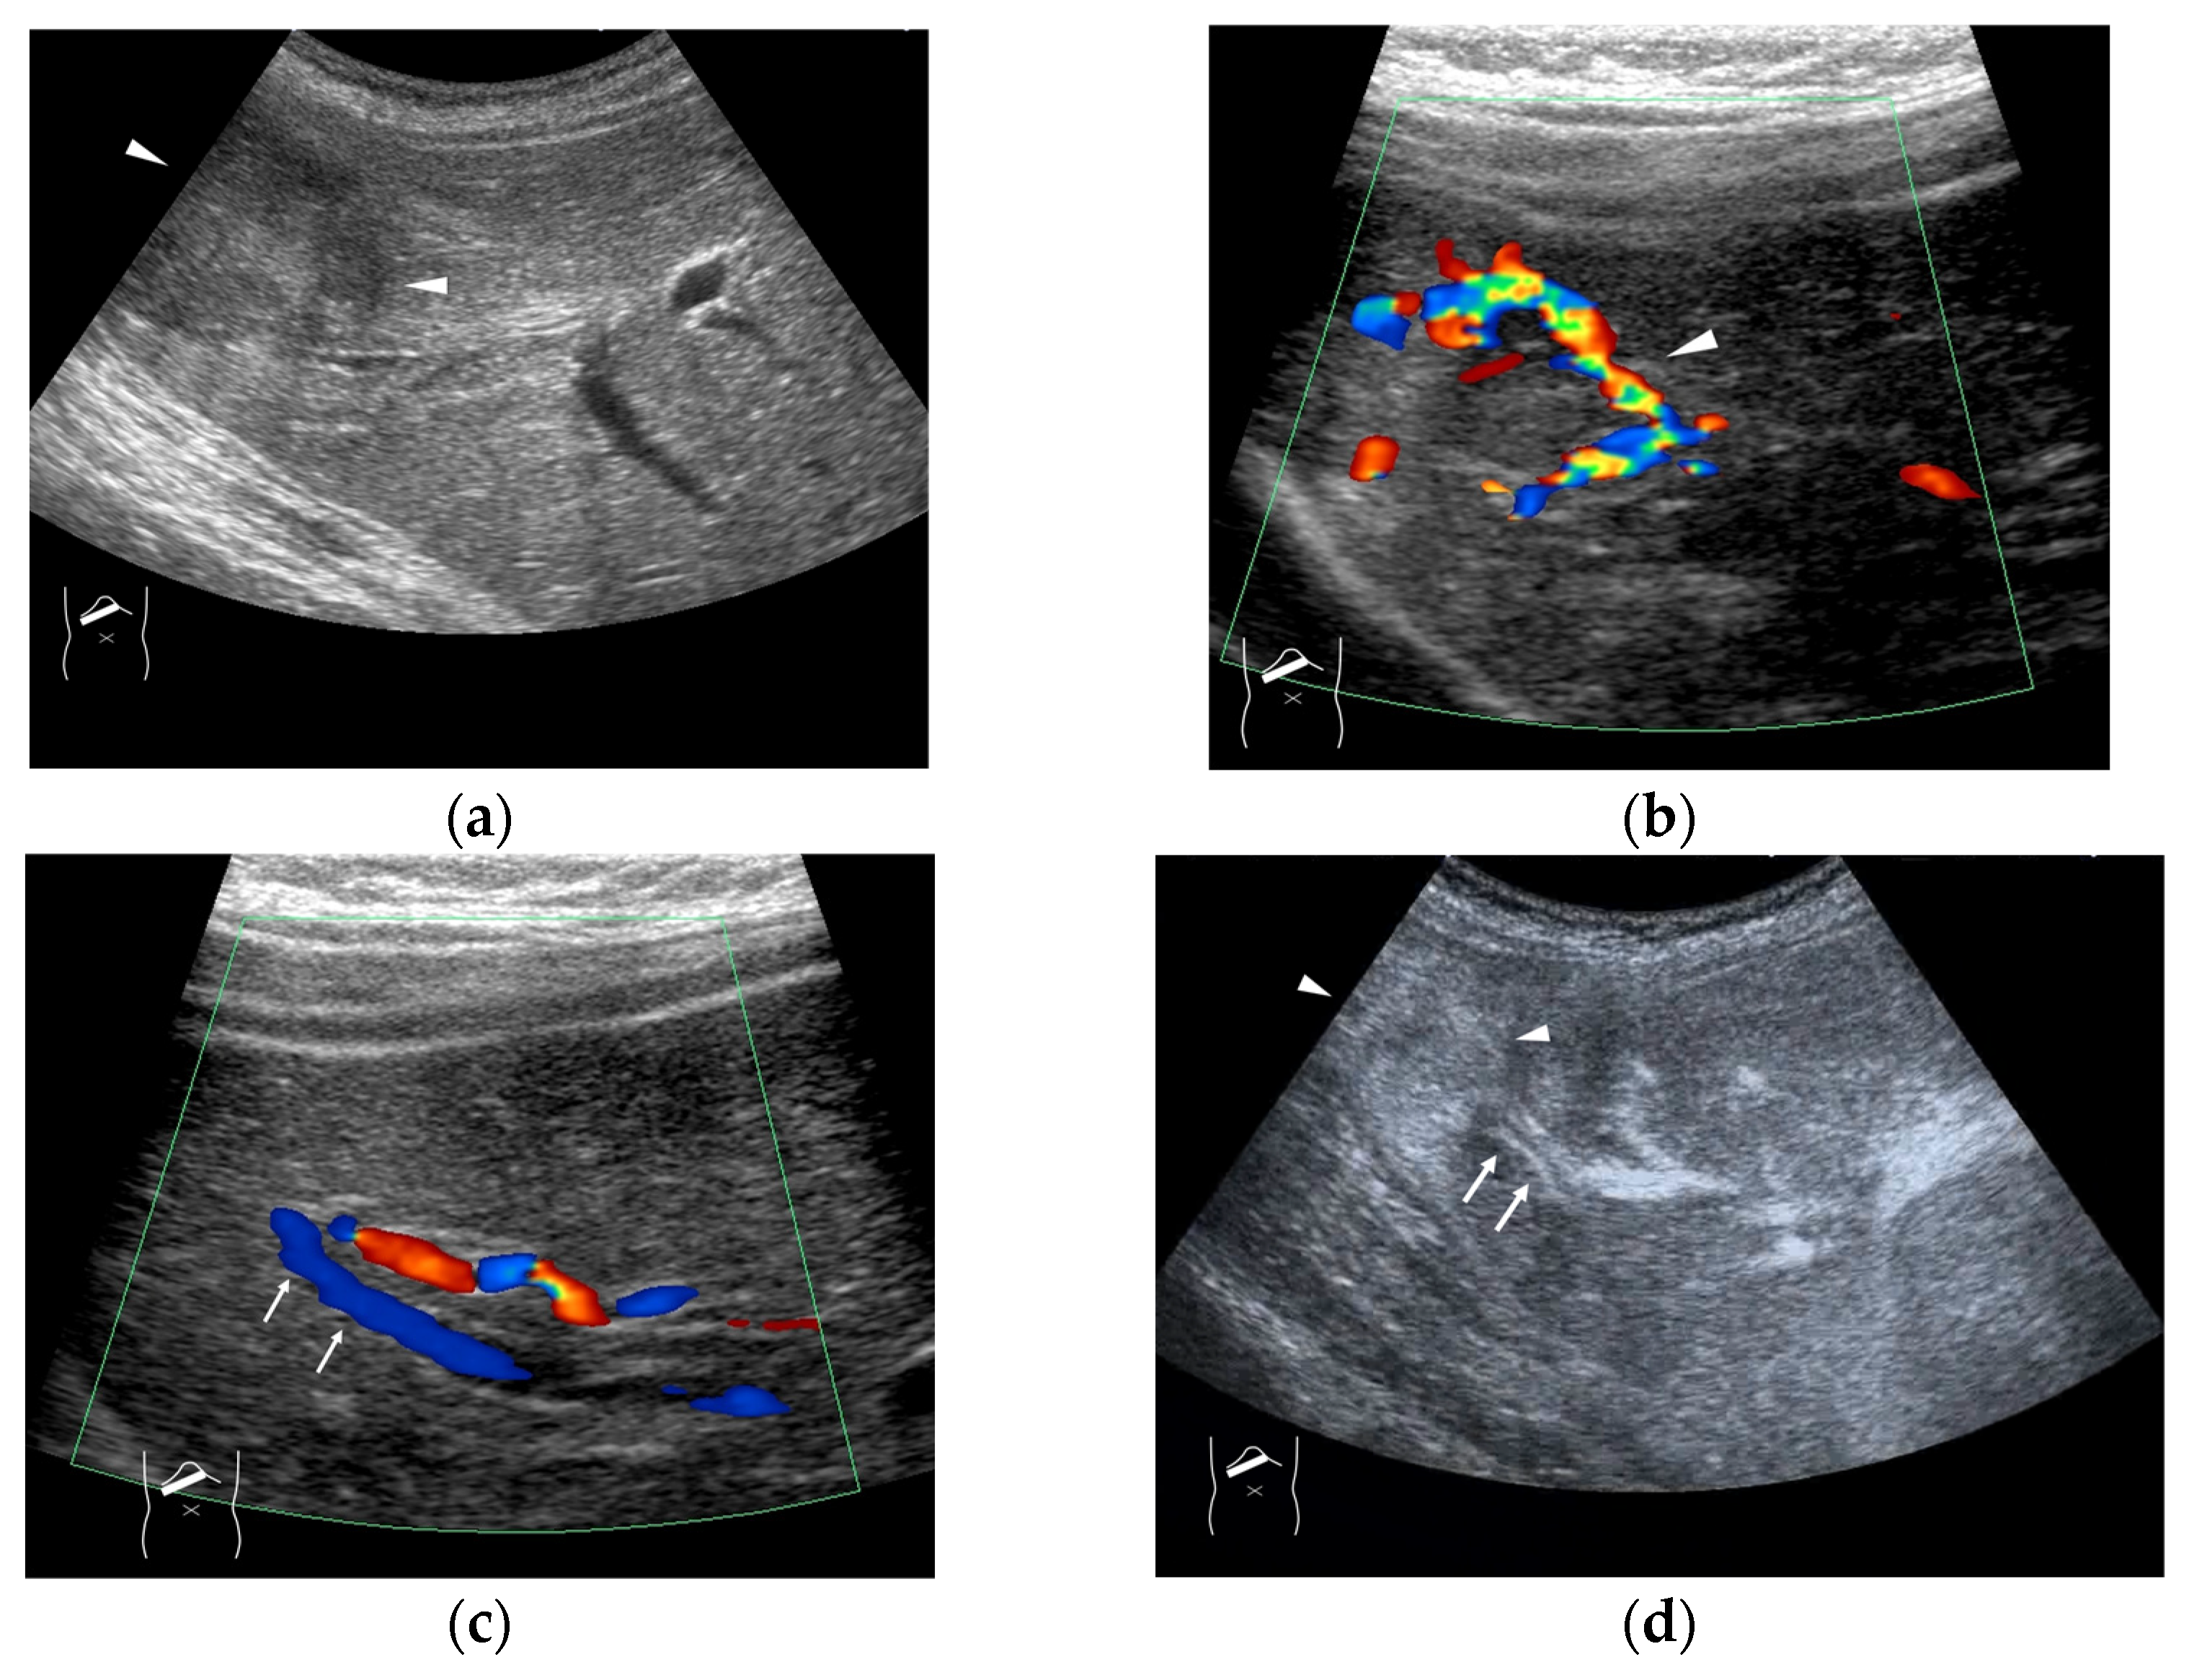

3. HV Hemodynamic Changes in Liver Tumors

4. HV Hemodynamic Changes (Vascular Shunts) in Non-Tumor-Related Livers

4.1. HHT-Related HV Abnormalities